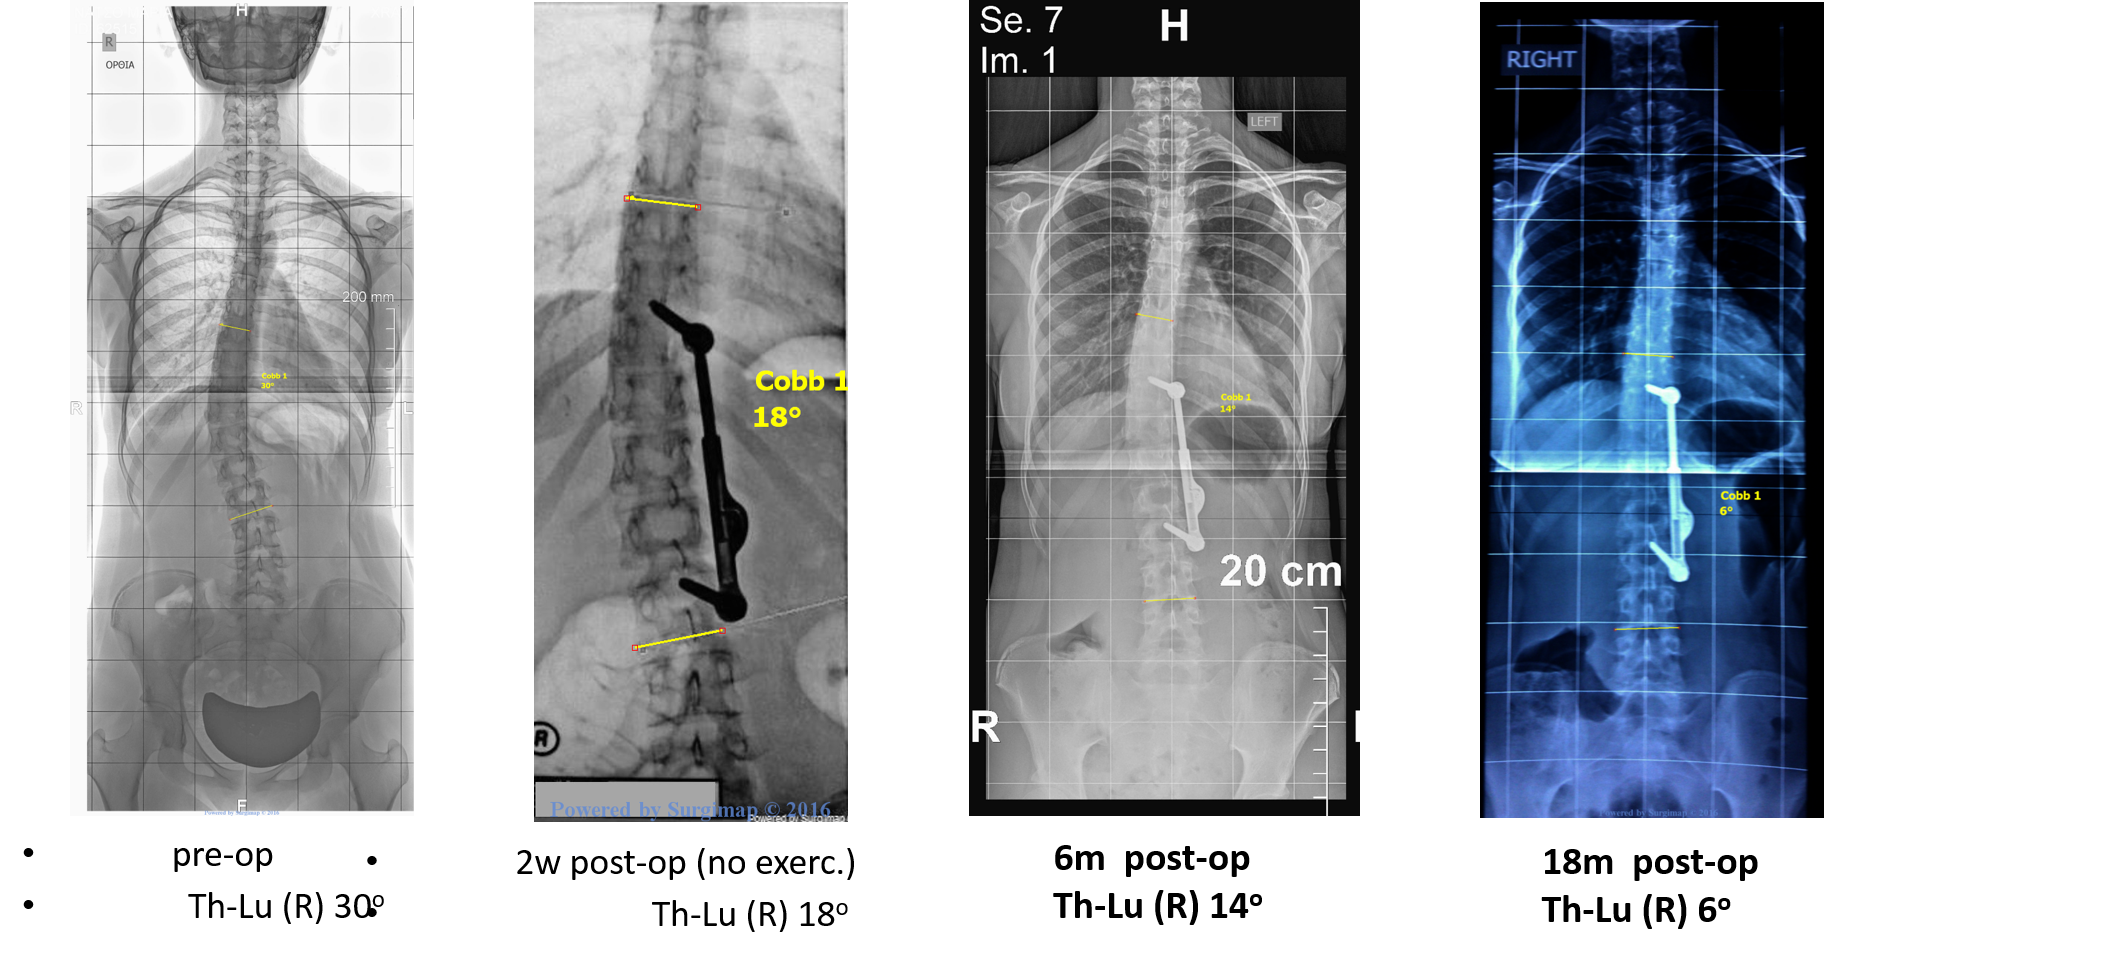

Τα αποτελέσματα της έρευνας έδειξαν πως ο μέσος όρος διόρθωσης της γωνίας Cobb, μετά την εφαρμογή του συστήματος ApiFix και των ασκήσεων με την μέθοδο Schroth, ήταν 40,1%. Η βοήθεια των ασκήσεων της μεθόδου Schroth φαίνεται να είναι καθοριστικής σημασίας, καθώς η ανάλυση πριν και μετά τις ασκήσεις, έδειξε βελτίωση περίπου 4,6 μοίρες ακόμα. Επίσης, οι ασκήσεις με την μέθοδο Schroth βελτίωσαν σημαντικά και την γωνία της στροφής της σκολίωσης (ATR) κατά 2,6 μοίρες, καθώς και τον πόνο και την εμφάνιση του ασθενούς, σύμφωνα με τα ειδικά ερωτηματολόγια που χρησιμοποιήθηκαν για τους σκοπούς της έρευνας. Οι ασθενείς με την μέθοδο Schroth έχουν μια εφ’όρου ζωής εκπαίδευση για την διατήρηση μιας διορθωμένης στάσης κατά τις καθημερινές τους δραστηριότητες, η οποία εξασφαλίζει την μακροπρόθεσμη σταθεροποίηση του θεραπευτικού αποτελέσματος.

Methods: Prospective case-series study (Level of Evidence IV). 6 females (mean age 15.6 years, Risser 3.7, Cobb angle 41.8ο, 2 Lenke Type I and 4 Lenke Type V curvatures) were treated with ApiFix system in Greece. All patients followed a Scoliosis Specific Exercises program for 6 months after operation, under the supervision of a Schroth Certified Physiotherapist. The outcome parameters analyzed were Cobb angle, Angle of Trunk Rotation (ATR), Aesthetics (measured by TAPS questionnaire and TRACE scale) and Pain (measured by Visual Analogue Scale). The average follow-up for the patients was 17.5 months. Unpaired student t-test was used for statistical analysis.

Results and Discussion: A significant Cobb angle correction of 40.08% (from 42.8ο to 25.7ο, p=0.017) was achieved for the whole group. Some of the patients did not have absolute indications for ApiFix treatment and this might restricted the final correction. One patient had a complication and underwent a revision surgery, due to a backup of the ratchet mechanism that was corrected by locking the mechanism. Another patient had no chance for elongation of the implant and further correction, due to improper length of the mechanism. A further analysis of the pre/post exercises result in the other 4 patients showed that Schroth method reduced the Cobb angle by 4.6ο (from 26.3ο to 21.7ο, p=0.53), the ATR by 2.3ο (from 10.5ο to 8.2ο, p=0.252), the TAPS score by 0.7 (from 3.2 to 3.9, p=0.113), the TRACE score by 2 (from 3.75 to 1.75, p=0.001) and the VAS score by 1.3 (from 2 to 0.7, p=0.04). Moreover, the Schroth exercises stabilized the secondary curvatures, normalized the sagittal plane in some cases and educated the patients to unload their spine and avoid mechanical forces by a specific training of Activities of Daily Living (ADL).

Conclusions and Significance: ApiFix system, with the assistance of Schroth method, can significantly decrease Cobb angle (40.08%, p=0.017) and treat AIS without spinal fusion. Schroth method exercises also further improved the Cobb angle (by 4.6ο), ATR, aesthetics and pain after operation. Schroth exercises, designed only by a Certified Physiotherapist, must be implemented after ApiFix operation in order to enhance the final treatment result. The proper choice of the most suitable patients with clear indications is of paramount importance, while better quality studies, larger samples and long-term results are needed in future research.